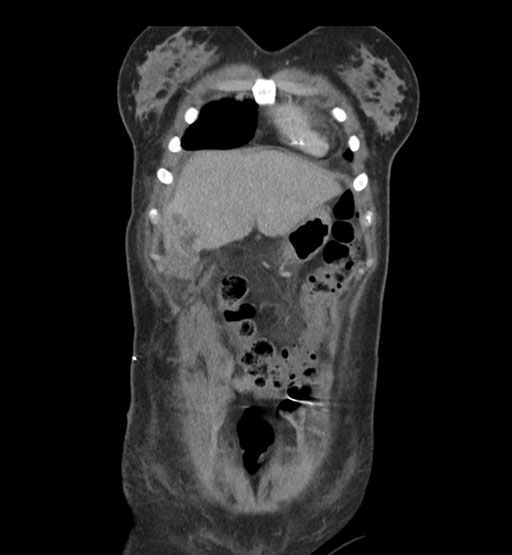

Coronal Venous